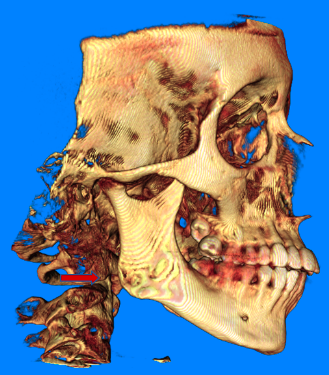

Para realizar un diagnóstico preciso, es crucial utilizar pruebas de imagen, como radiografías panorámicas, que permiten descartar patologías dentales como causa de dolor referido, así como identificar anormalidades en los cóndilos de la rama mandibular que puedan indicar un proceso degenerativo incipiente. Otra prueba de gran utilidad es la tomografía computarizada de haz cónico, que proporciona imágenes detalladas de las estructuras óseas de la articulación, como quistes subcondrales, erosiones, esclerosis generalizada u osteofitos. Sin embargo, esta técnica no permite visualizar el disco articular en su totalidad. Para obtener una evaluación completa de la posición y morfología del disco, así como para detectar cambios óseos degenerativos y derrames articulares, se recomienda el uso de resonancia magnética.